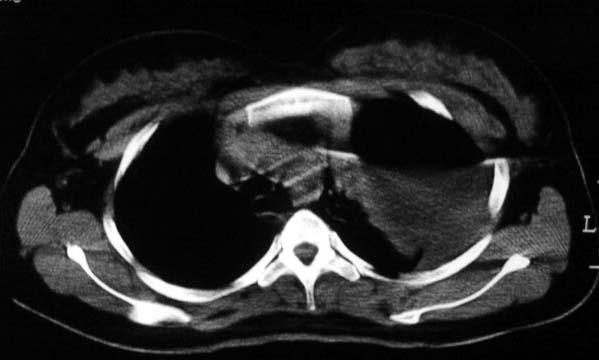

标题: CT5517:女性、24岁,反复胸痛、气促不能平卧半月。

左肺可见二个含气或液气的囊状影,左肺段支气管、左肺动脉显示不清,纵隔右移,考虑:左肺支气管肺囊肿,左肺发育不良,纵隔疝。

左侧气液腔与胃腔影相连,考虑膈疝。钡餐检查有助于诊断。

我看这是膈疝,在纵隔窗第六\\七幅图像上可见胃粘膜影,再者可见两个腔影,这在液气胸是不会有的.

支持膈疝,纵隔窗内可见消化道的内容物。

“反复胸痛、气促不能平卧半月”。+影像学表现=膈疝

谨慎!喝钡透视一下吧。冒然报一液气胸,临床再穿刺引流结果把胃戳个大洞就麻烦了!

液气胸 怎么会有2 个大腔?

左肺发育不良、支气管囊肿 应该纵隔左移的多吧

还是个膈疝